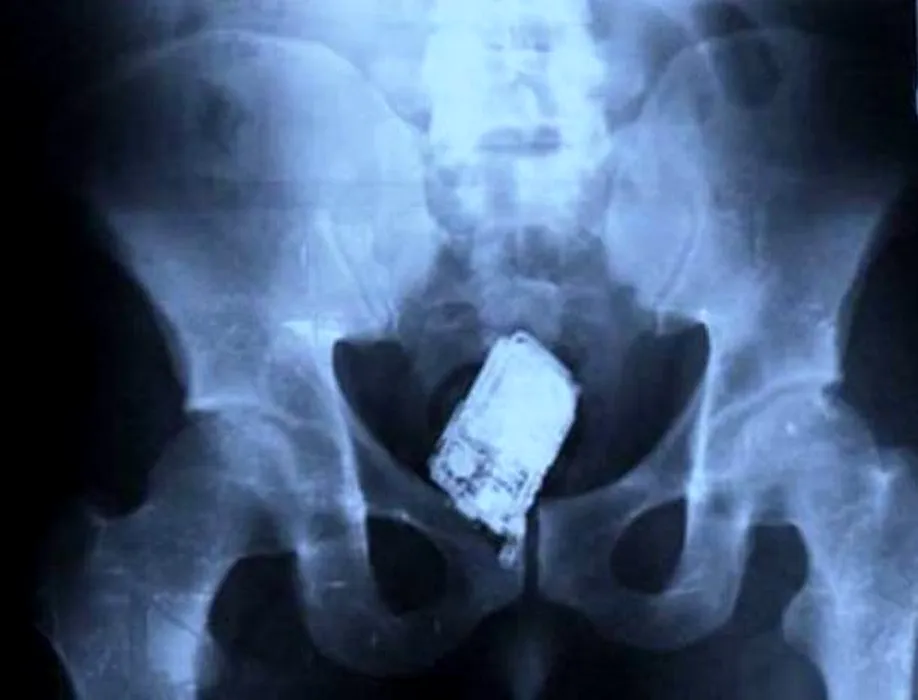

Cele mai ciudate lucruri pe care doctorii le-au găsit în stomacul pacienților. GALERIE FOTO